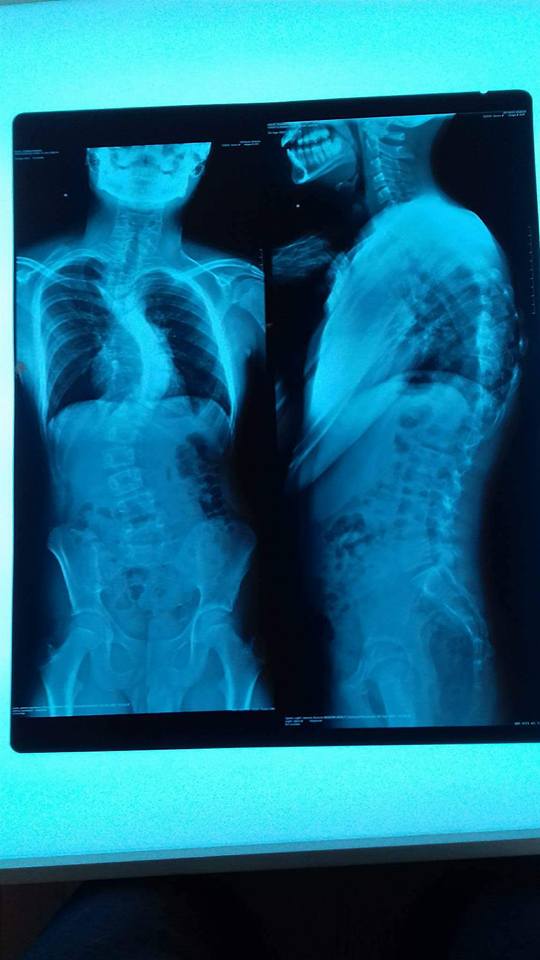

Erhard are 12 ani! La vârsta de 5 ani a fost diagnosticat cu sindromul Asperger, o tulburare din spectrul autist. În urma cu 3 ani, a apărut scolioza. Pe atunci scolioza avea 23 de grade. Au urmat ședințe inot, kinetoterapie, gimnastica medicinala, corset. Camera lui am dotat-o cu spalier și pat special.

Scolioza s-a agravat...a ajuns la peste 70 de grade și prezintă 3 curburi. La București i-au descoperit și scifoza. Singura șansă este o operație complexa pe coloana care durează intre 9 si 12 ore.